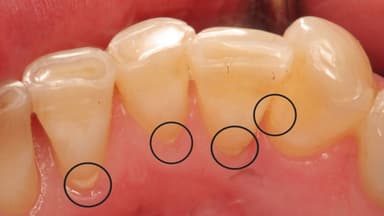

Các dạng cao răng phổ biến bao gồm cao răng trên thân răng và cao răng dưới nướu. Trong đó:

– Cao răng trên thân răng thường có màu vàng nâu hoặc nâu đỏ và chúng thường nằm ở vị trí dễ quan sát như quanh cổ răng.

– Cao răng dưới nướu là loại cao răng cực kỳ nguy hiểm vì chúng ẩn giấu ở dưới nướu. Chúng khó nhìn thấy và không thể loại bỏ bằng cách thông thường.

Thông thường, các mảng vôi răng ở dưới nướu thường có màu nâu sậm. Sau đó, chúng có thể chuyển sang màu xanh đen. Khi chuyển màu, cao răng trở nên cứng hơn so với phần cao răng ở trên nướu. Một số người thường nghĩ rằng vôi răng ở dưới nướu hình thành do sự kéo dài trực tiếp từ các cao răng trên nướu. Tuy nhiên, thực tế chúng được hình thành từ quá trình khoáng hóa mảng bám ở dưới nướu.